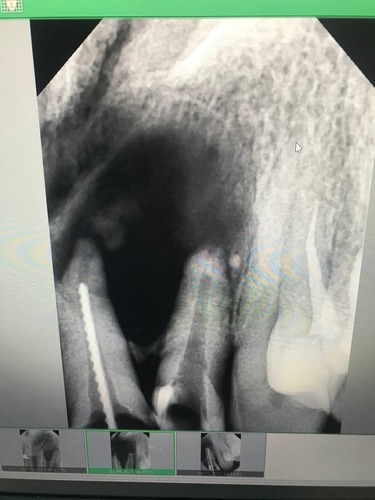

Терапевт сделал снимок, не увидел на нём ничего предосудительного и провёл стандартное лечение: вскрыл причинный зуб, обработал канал и установил лекарство, чтобы купировать начавшееся воспаление. Словом, поначалу всё выглядело совершенно обычно. Но дальше началось самое интересное.

Снимок того пациента и причинный зуб

У этого пациента была очень нетипичная картина воспаления. Обычно, если происходит что-то подобное, раздувается флюс, а у него его не было. Иногда флегмону предваряет остеомиелит, его можно было бы увидеть на снимке, но тут гной полностью ушёл в дно полости рта.

Вот так выглядит на снимке явное воспаление

Рентген и КТ в его случае оказались бесполезны. Рентгеновские лучи просвечивают мягкие ткани насквозь, поэтому подобные вещи так не увидеть в принципе. На КТ ткани видны, но не видно воспаление. То есть, например, на месте кисты мы бы увидели пробел в костной ткани, по которому было бы понятно, что внутри что-то есть. А в этом случае единственное, что нам удалось разглядеть, — это незначительное разрежение ткани вокруг зуба, которое не говорит вообще ни о чём.